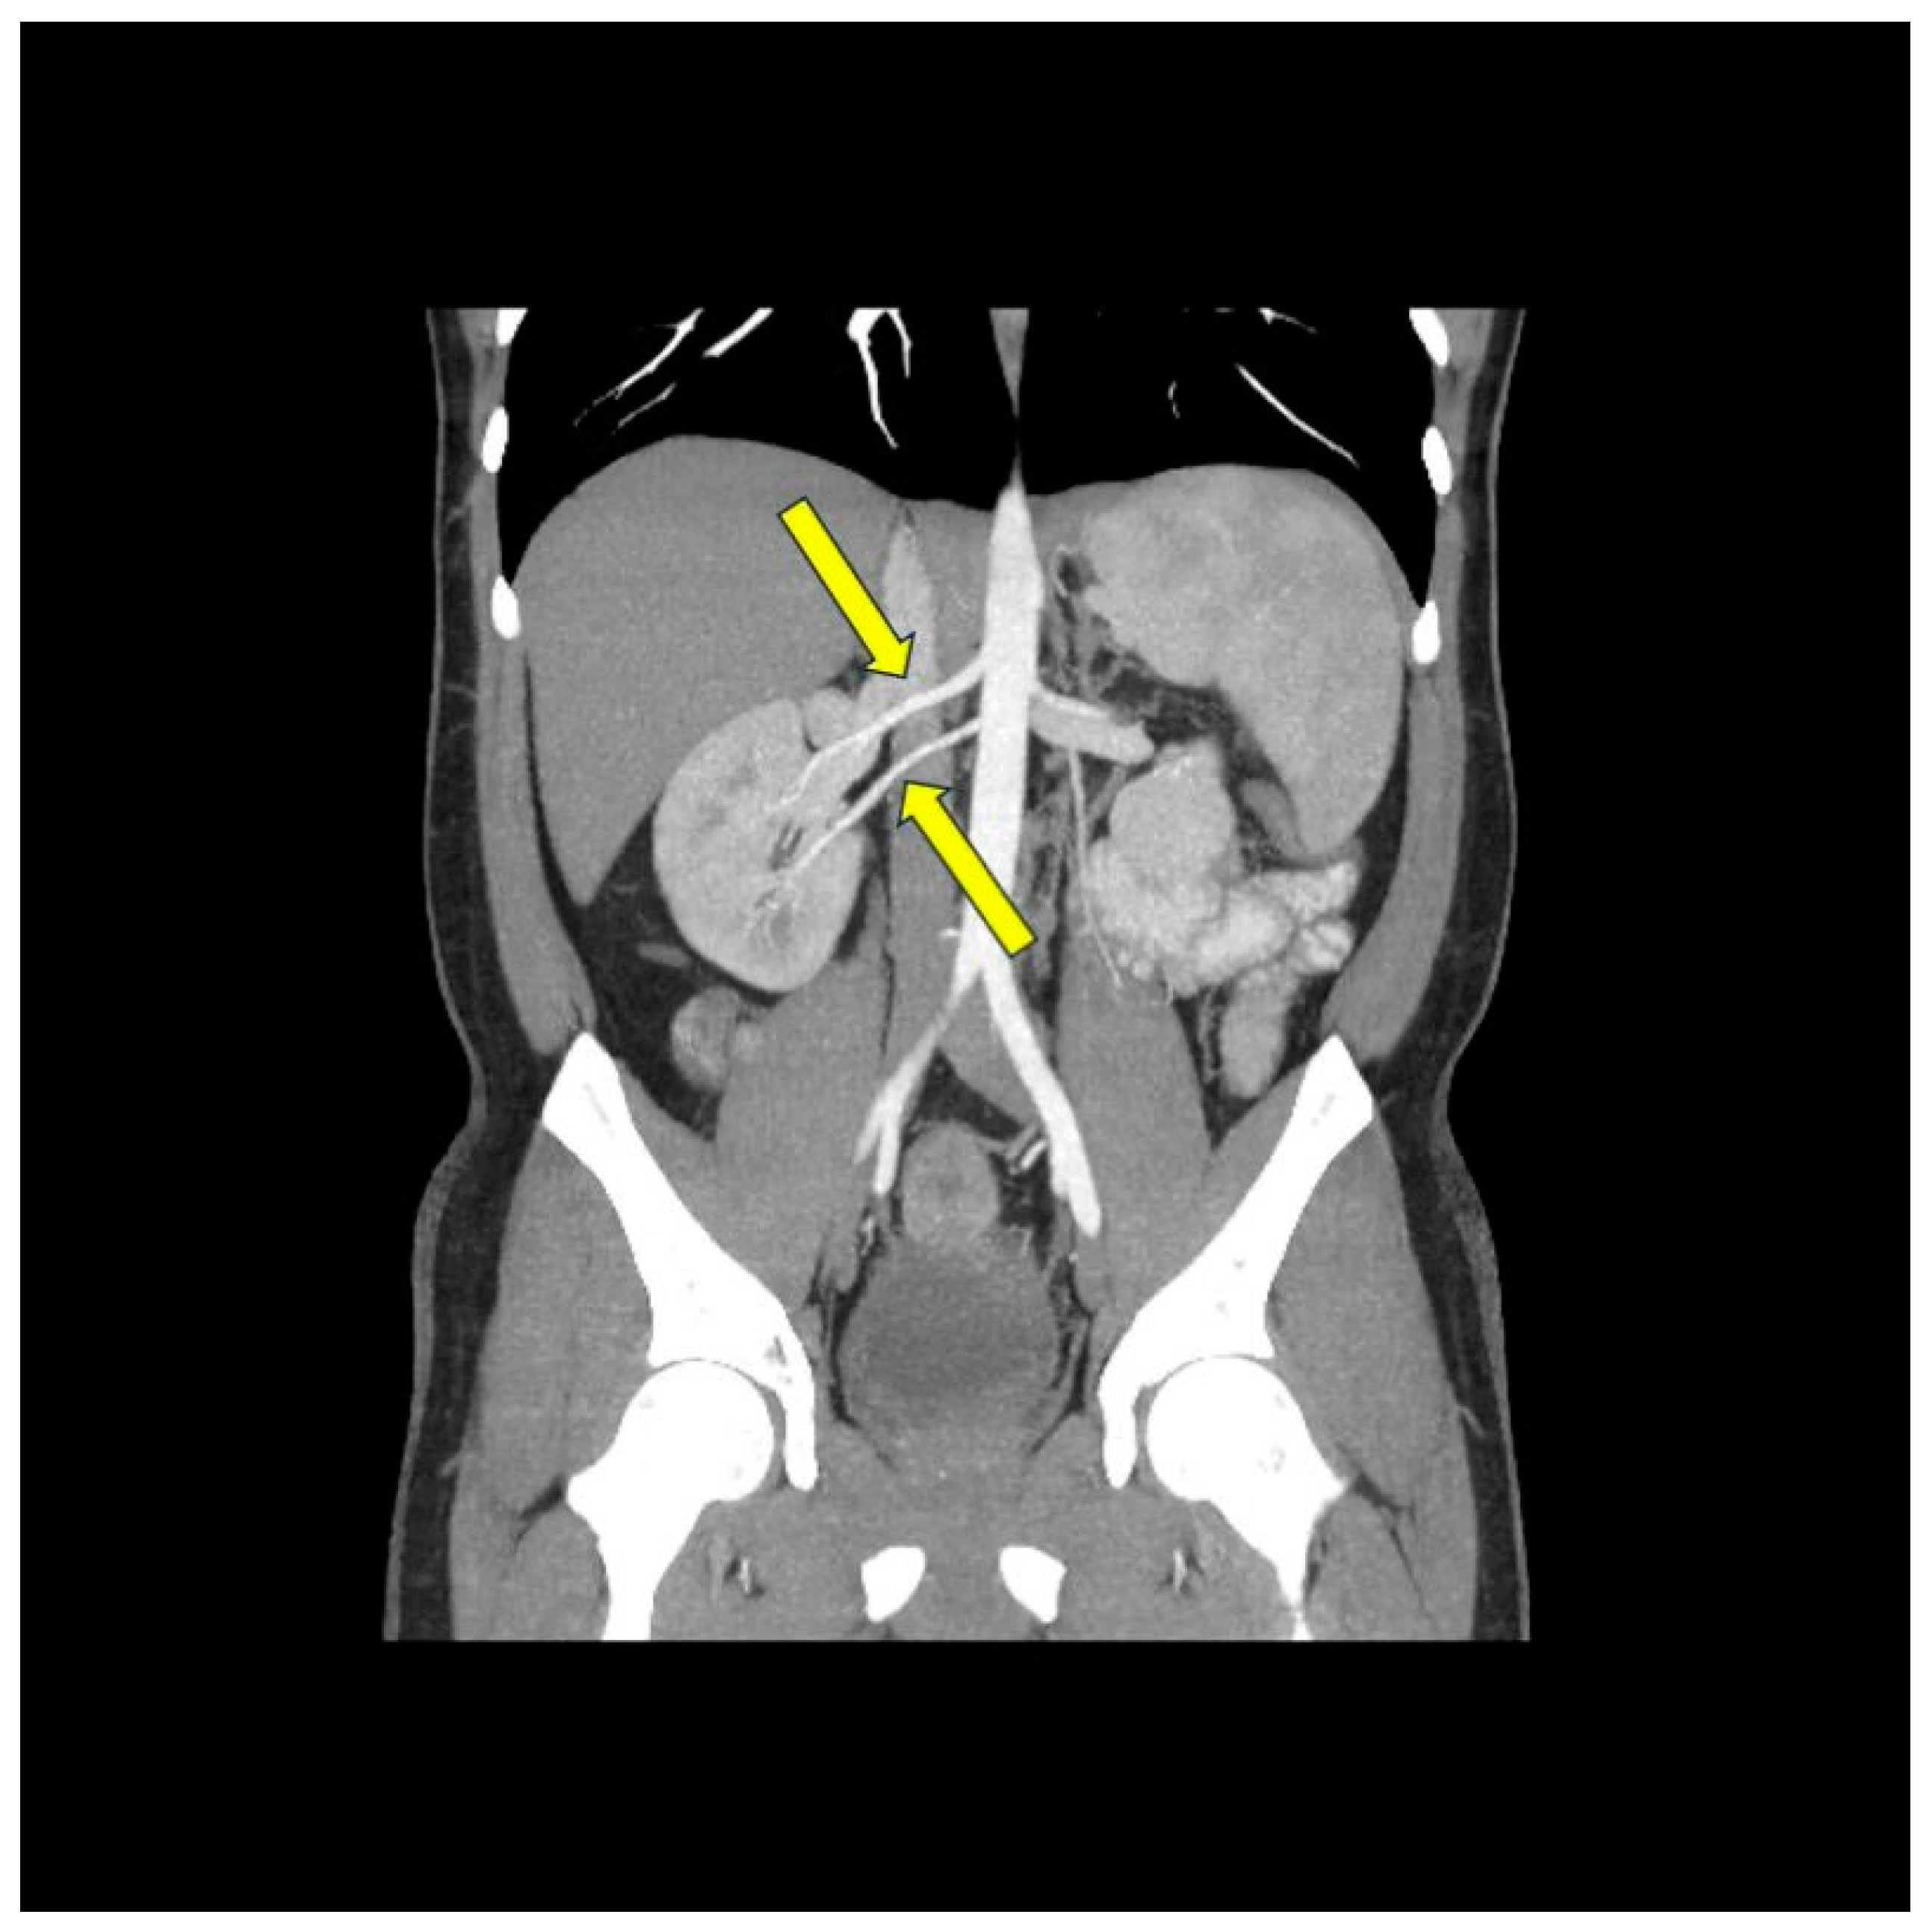

- Możeńska, O.; Rosiak, M.; Gziut, A.; Gil, R.J.; Kosior, D.A. First-in-man experience with renal denervation of multiple renal arteries in a patient with solitary kidney and resistant hypertension. Pol. Arch. Intern. Med. 2017, 127, 60–62. [Google Scholar] [CrossRef]

- Bartus, K.; Podolec, J.; Sadowski, J.; Litwinowicz, R.; Zajdel, W.; Bartus, M.; Konstanty-Kalandyk, J.; Dziewierz, A.; Trąbka, R.; Bartus, S.; et al. Blood pressure reduction in patients with accessory renal arteries and bilateral single renal arteries after catheter-based renal denervation: A prospective study with 3-year follow-up. Pol. Arch. Intern. Med. 2017, 127, 423–428. [Google Scholar] [CrossRef][Green Version]

- Song, W.H.; Baik, J.; Choi, E.-K.; Lee, H.-Y.; Kim, H.H.; Park, S.-M.; Jeong, C.W. Quantitative analysis of renal arterial variations affecting the eligibility of catheter-based renal denervation using multi-detector computed tomography angiography. Sci. Rep. 2020, 10, 19720. [Google Scholar] [CrossRef] [PubMed]